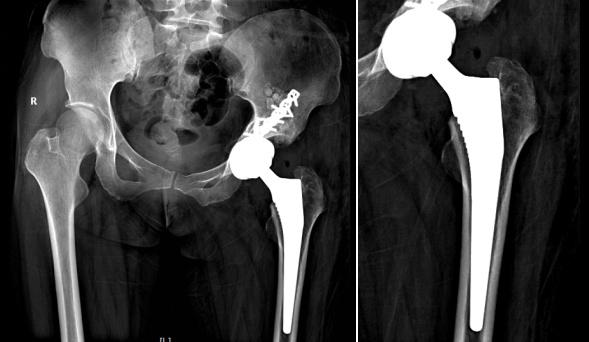

近日,福建医科大学附属协和医院关节外科陈敏主任团队收治了一名患者,罕见地从其髋关节中取出近300颗软骨瘤,完成高难度“清石之战”。   女子疼得没法走路   检查结果让医生大吃一惊   王女士(化名)今年40岁   10年前的一次车祸   让她的左侧髋关节严重骨折   虽经手术固定   但髋关节内滑膜组织   在经年累月的摩擦中悄然 “蜕变”   近期   髋关节疼痛逐渐加重   已经严重影响了日常活动   辗转多家医院就诊无果后   王女士来到了   福建医科大学附属协和医院   关节外科陈敏主任团队接诊了她   通过髋关节X线扫描,结果令医生都感到吃惊不已。原来,王女士的髋关节腔内竟有近300颗大小不一的滑膜软骨瘤,最大直径达2厘米。这些“关节顽石”引发严重骨性关节炎,股骨头严重磨损,关节间隙几乎消失殆尽。

X线扫描显示,王女士髋关节腔内布满滑膜软骨瘤。

最终   王女士被确诊为   髋关节滑膜软骨瘤病   髋关节滑膜软骨瘤病(SC)是一种多发生在关节腔内的罕见良性病变。发病率仅为1/10万,多见于30~50岁的成年男性,男女发病比为3:1,多累及单关节,膝关节最常受累及,次之为肩、肘、髋关节。   外伤是本病的诱发因素,滑膜内滑囊组织内的多功能间质干细胞向软骨化生,形成软骨或骨-软骨游离体。早期无特异性,活动后髋关节酸胀不适,随着病情加重可出现髋关节疼痛,晚期出现髋关节活动受限,其中屈曲、外旋多见。   “废墟”上重建关节   手术顺利完成   “想要解决髋关节问题,除了取石,还需要在‘废墟’上重建关节。”陈敏主任说。   首先,由于王女士曾接受过髋关节内固定手术,致密瘢痕组织会影响手术暴露,并且内固定螺钉也会阻碍髋臼假体的安装。其次,要耐心地尽可能清除游离体,切除可能是病变来源的滑膜及滑囊组织,又要保留健康滑膜组织。   针对王女士的病情,陈敏主任带领其团队成员制定了个性化的手术方案——左侧人工全髋关节置换术+滑膜软骨瘤病病灶清除+游离体取出+髋臼骨折内固定取出术。

术后复查影像显示,王女士的软骨瘤已全部取出。